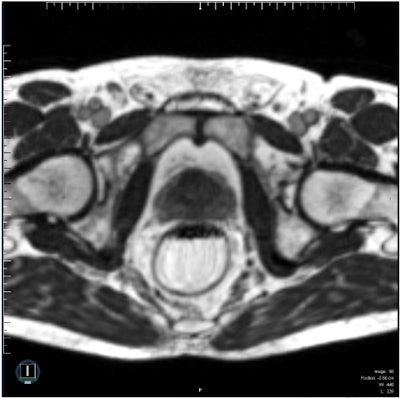

A clinical image of a prostate produced using a steady-state TrueFISP MR sequence acquired on a ViewRay 0.35-tesla MRIdian system in 25 seconds. Reprinted from Int. J. Radiat. Oncol. Biol. Phys. doi: 10.1016/j.ijrobp.2017.10.020 © 2017, with permission from Elsevier."By acquiring MR images prior to each fraction, we can produce a new radiotherapy plan for that day, adjusted for any changes in anatomy," Pathmanathan explained. "With MR guidance, this can be further adjusted whilst the patient is having the radiotherapy delivered, to take into account intrafractional movement of the prostate and the 'bystander' organs-at-risk."